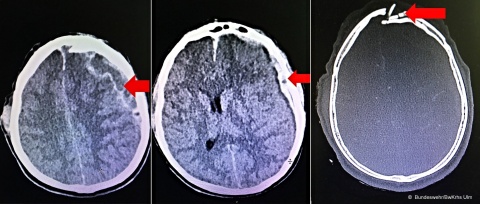

Da Romeo somnolent war und eine sichtbare Schussverletzung im Gesicht und Hals hatte, wurde er direkt in den Schockraum eingeliefert. Der Schusskanal verlief von links nach rechts, durch das Kinn und den Hals, über die rechte Schulter in den Thorax. Dabei hatte das Projektil die rechte Clavicula durchschlagen, die 1.–4. Rippe frakturiert und die Pleura penetriert. Der Atemweg war frei. Der Patient wies ein spürbares Emphysem am rechten Thorax auf. Das führte auch mit Blick auf den Mechanismus der Verletzung zu der frühen Entscheidung für die Thoraxdrainage. Da der Patient starke Schmerzen hatte, wurde er mit Ketanest und Midazolam analgosediert. Obwohl ich vorher schon unter Anleitung von Ärzten einige Drainagen gelegt und Übung in der Analgesie hatte, war es eine wichtige Erfahrung, diese Entscheidung eigenverantwortlich zu treffen und diese bei der Übergabe an den Arzt zu vertreten und überprüfen zu lassen. Auch wenn es klinisch eindeutig war, musste ich mich das erste Mal für einen lebensrettenden minimalen chirurgischen Eingriff entscheiden.